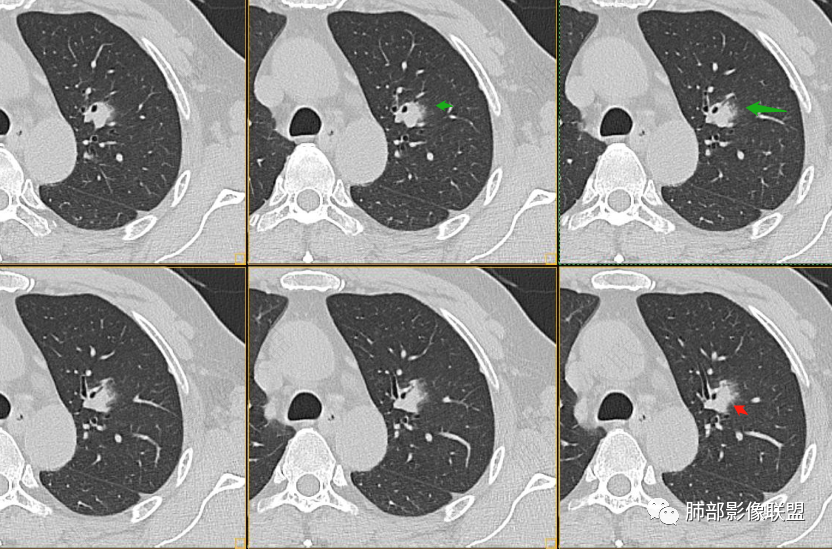

1、连续3年观察,病灶逐步增大,符合惰性恶性肿瘤。2、支气管壁增厚,腔内内壁无变化——病灶长轴沿支气管周围蔓延;朝外走,内侧没有,提示病灶间质为主,与支气管无关。

3、GGO长期存在,朝外蔓延,支持恶性特点。

支持淋巴瘤的关键点:1、间质为主;2、与支气管无关;3、边缘GGO的长期存在支持恶性

因为与支气管无关不支持腺癌,还是要警惕淋巴瘤。